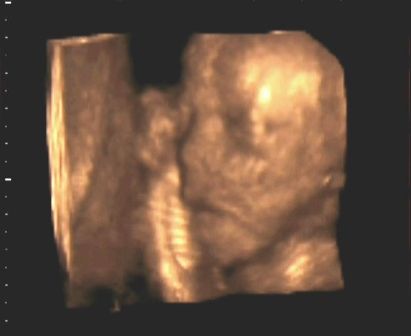

Az uh....

Utolsó alkalommal így csak láthattam még Zsófimat.

Viszont nem voltam 3d-s uhn sajnos. De nem is lényeg mostmár.